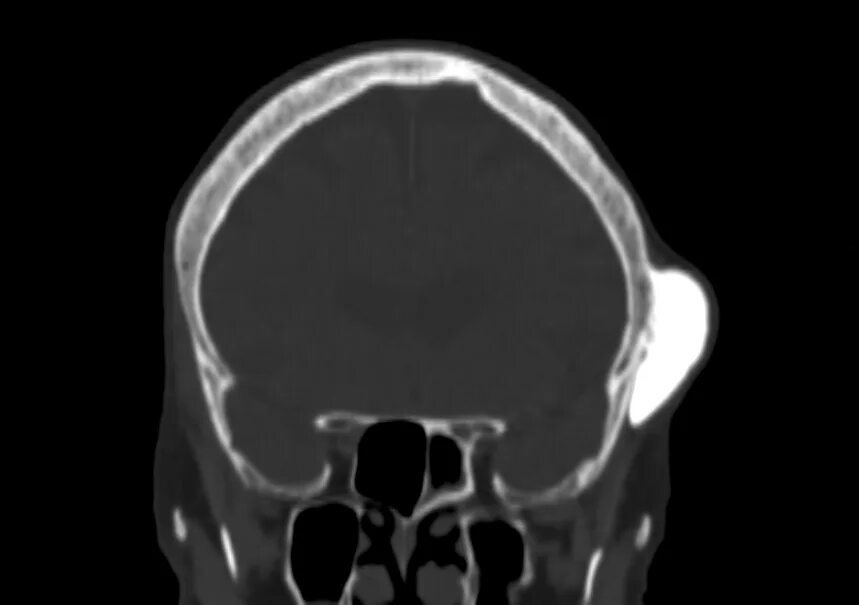

Череп на кт